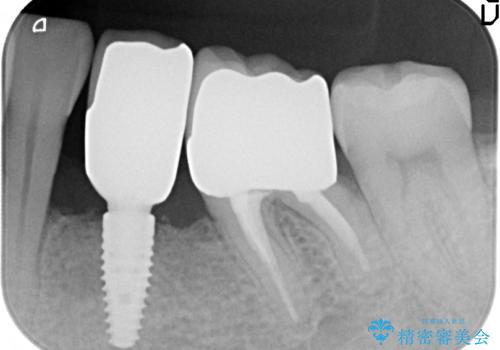

歯列矯正は御希望されなかったため左下4、5番目の歯を抜歯し、インプラントによる欠損補綴を行いました。

左下6も再根管治療後、オールセラミッククラウンによる補綴を行いました。

オールセラミッククラウンについて

今回用いたオールセラミッククラウンはジルコニアフレームという白い素材の上にセラミックを盛っているため、審美性が非常に高いのが特徴です。

また、ジルコニアは人工ダイヤモンドの材料にも使われているほど高い強度を持っており、そのためオールセラミッククラウンは審美性だけでなく、奥歯やブリッジの補綴も可能とするクラウンです。